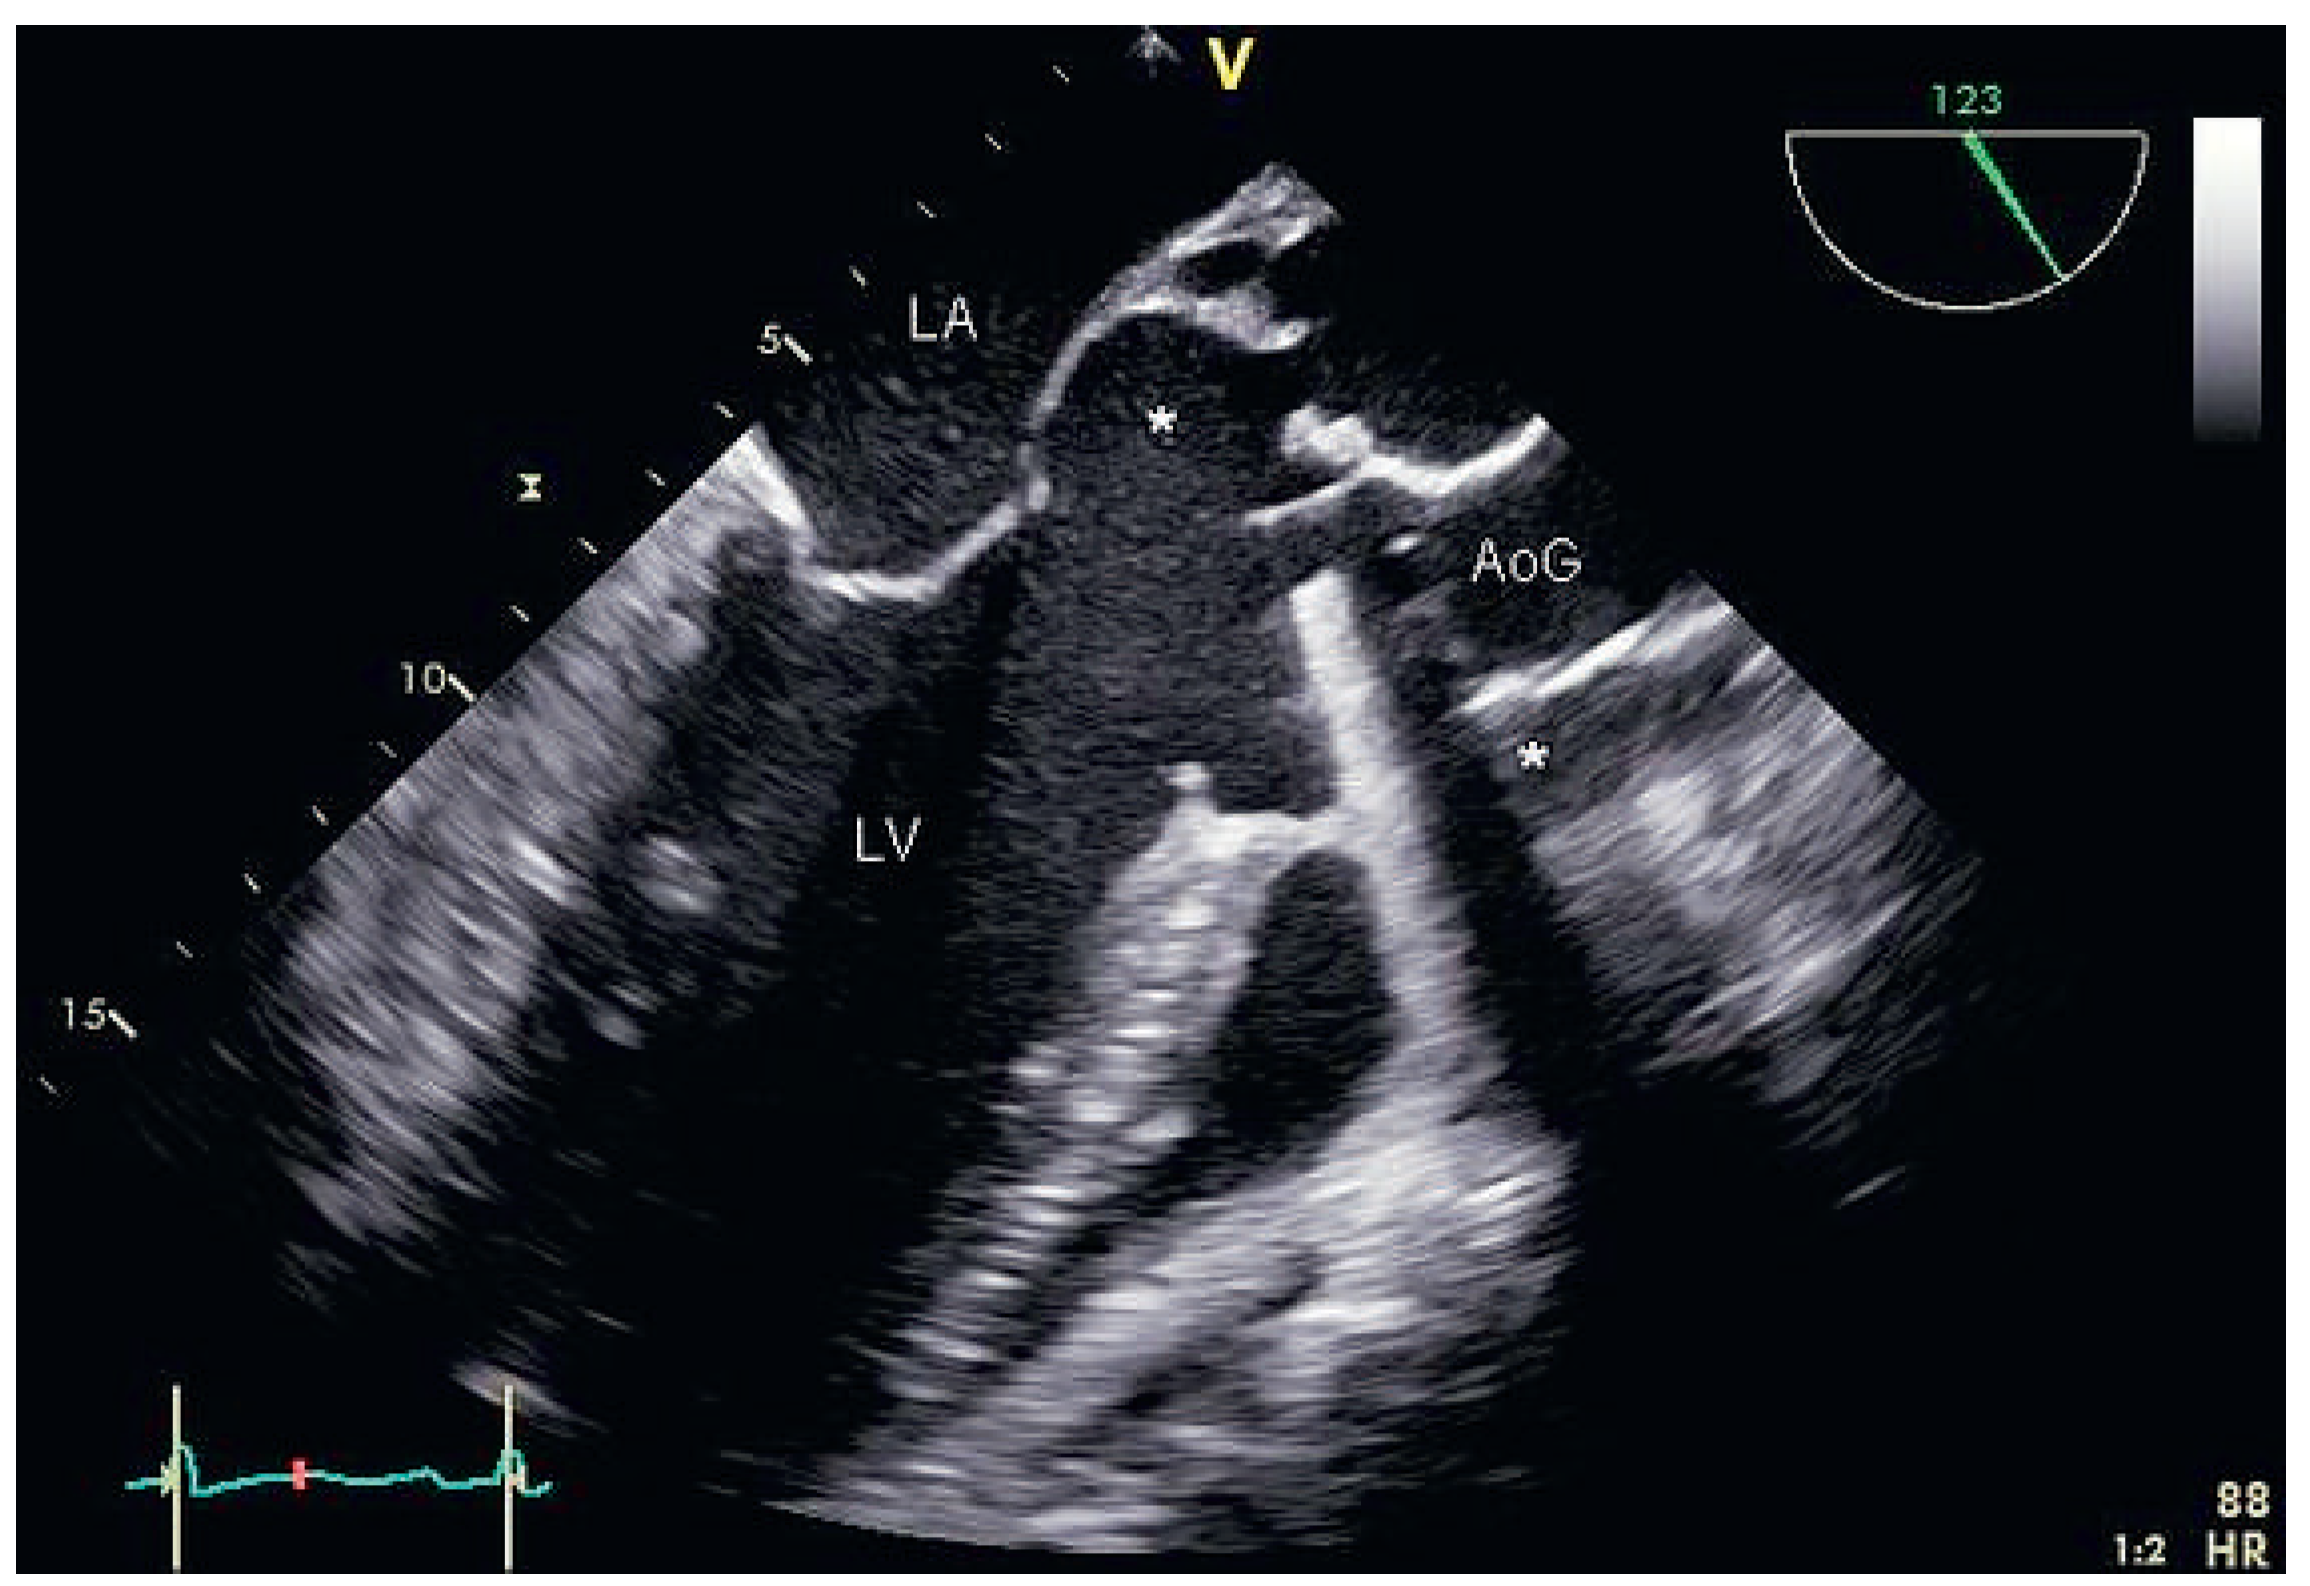

Partial Aortic Graft Disconnection Due to Endocarditis: A Rare Cause of Dynamic Coronary Artery Compression